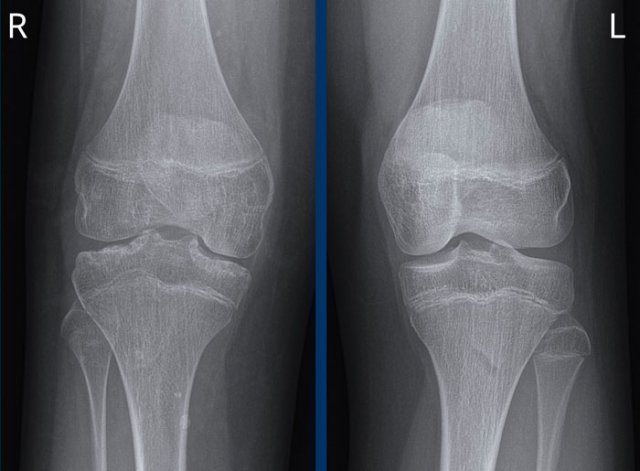

Cartilage

Degenerative diseases affect the cartilage non-uniformly or asymmetrically, since this is the result of mechanical load, which is not evenly distributed throughout the joint.

Inflammatory diseases affect the cartilage uniformly, since the synovitis is present in the entire joint.

Click on image to enlarge. Click on image to enlarge.

1. Typical osteoarthritis with cartilage loss on the medial side, subchondral sclerosis and osteophytes.

2. There is uniform cartilage loss.

There are no osteophytes.

In such a case your first thought should be inflammatory joint disease.